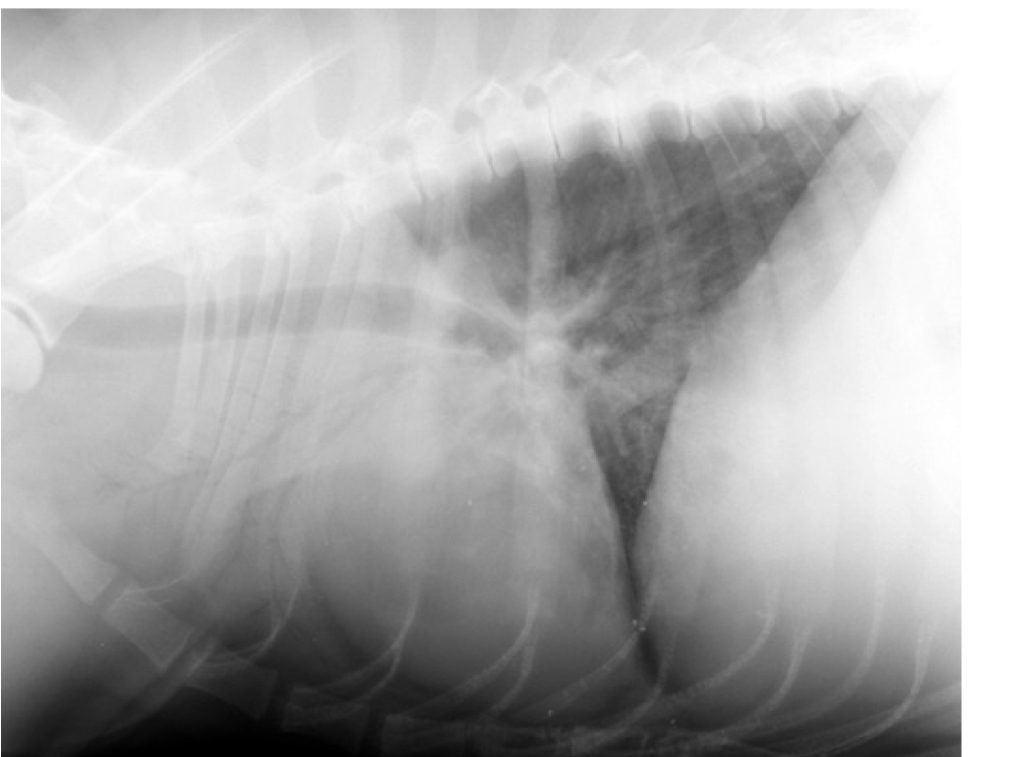

14

Q

what lung pattern and ddx

A

cranioventral

Ddx: pneumonia, hemorrhage, neoplasia